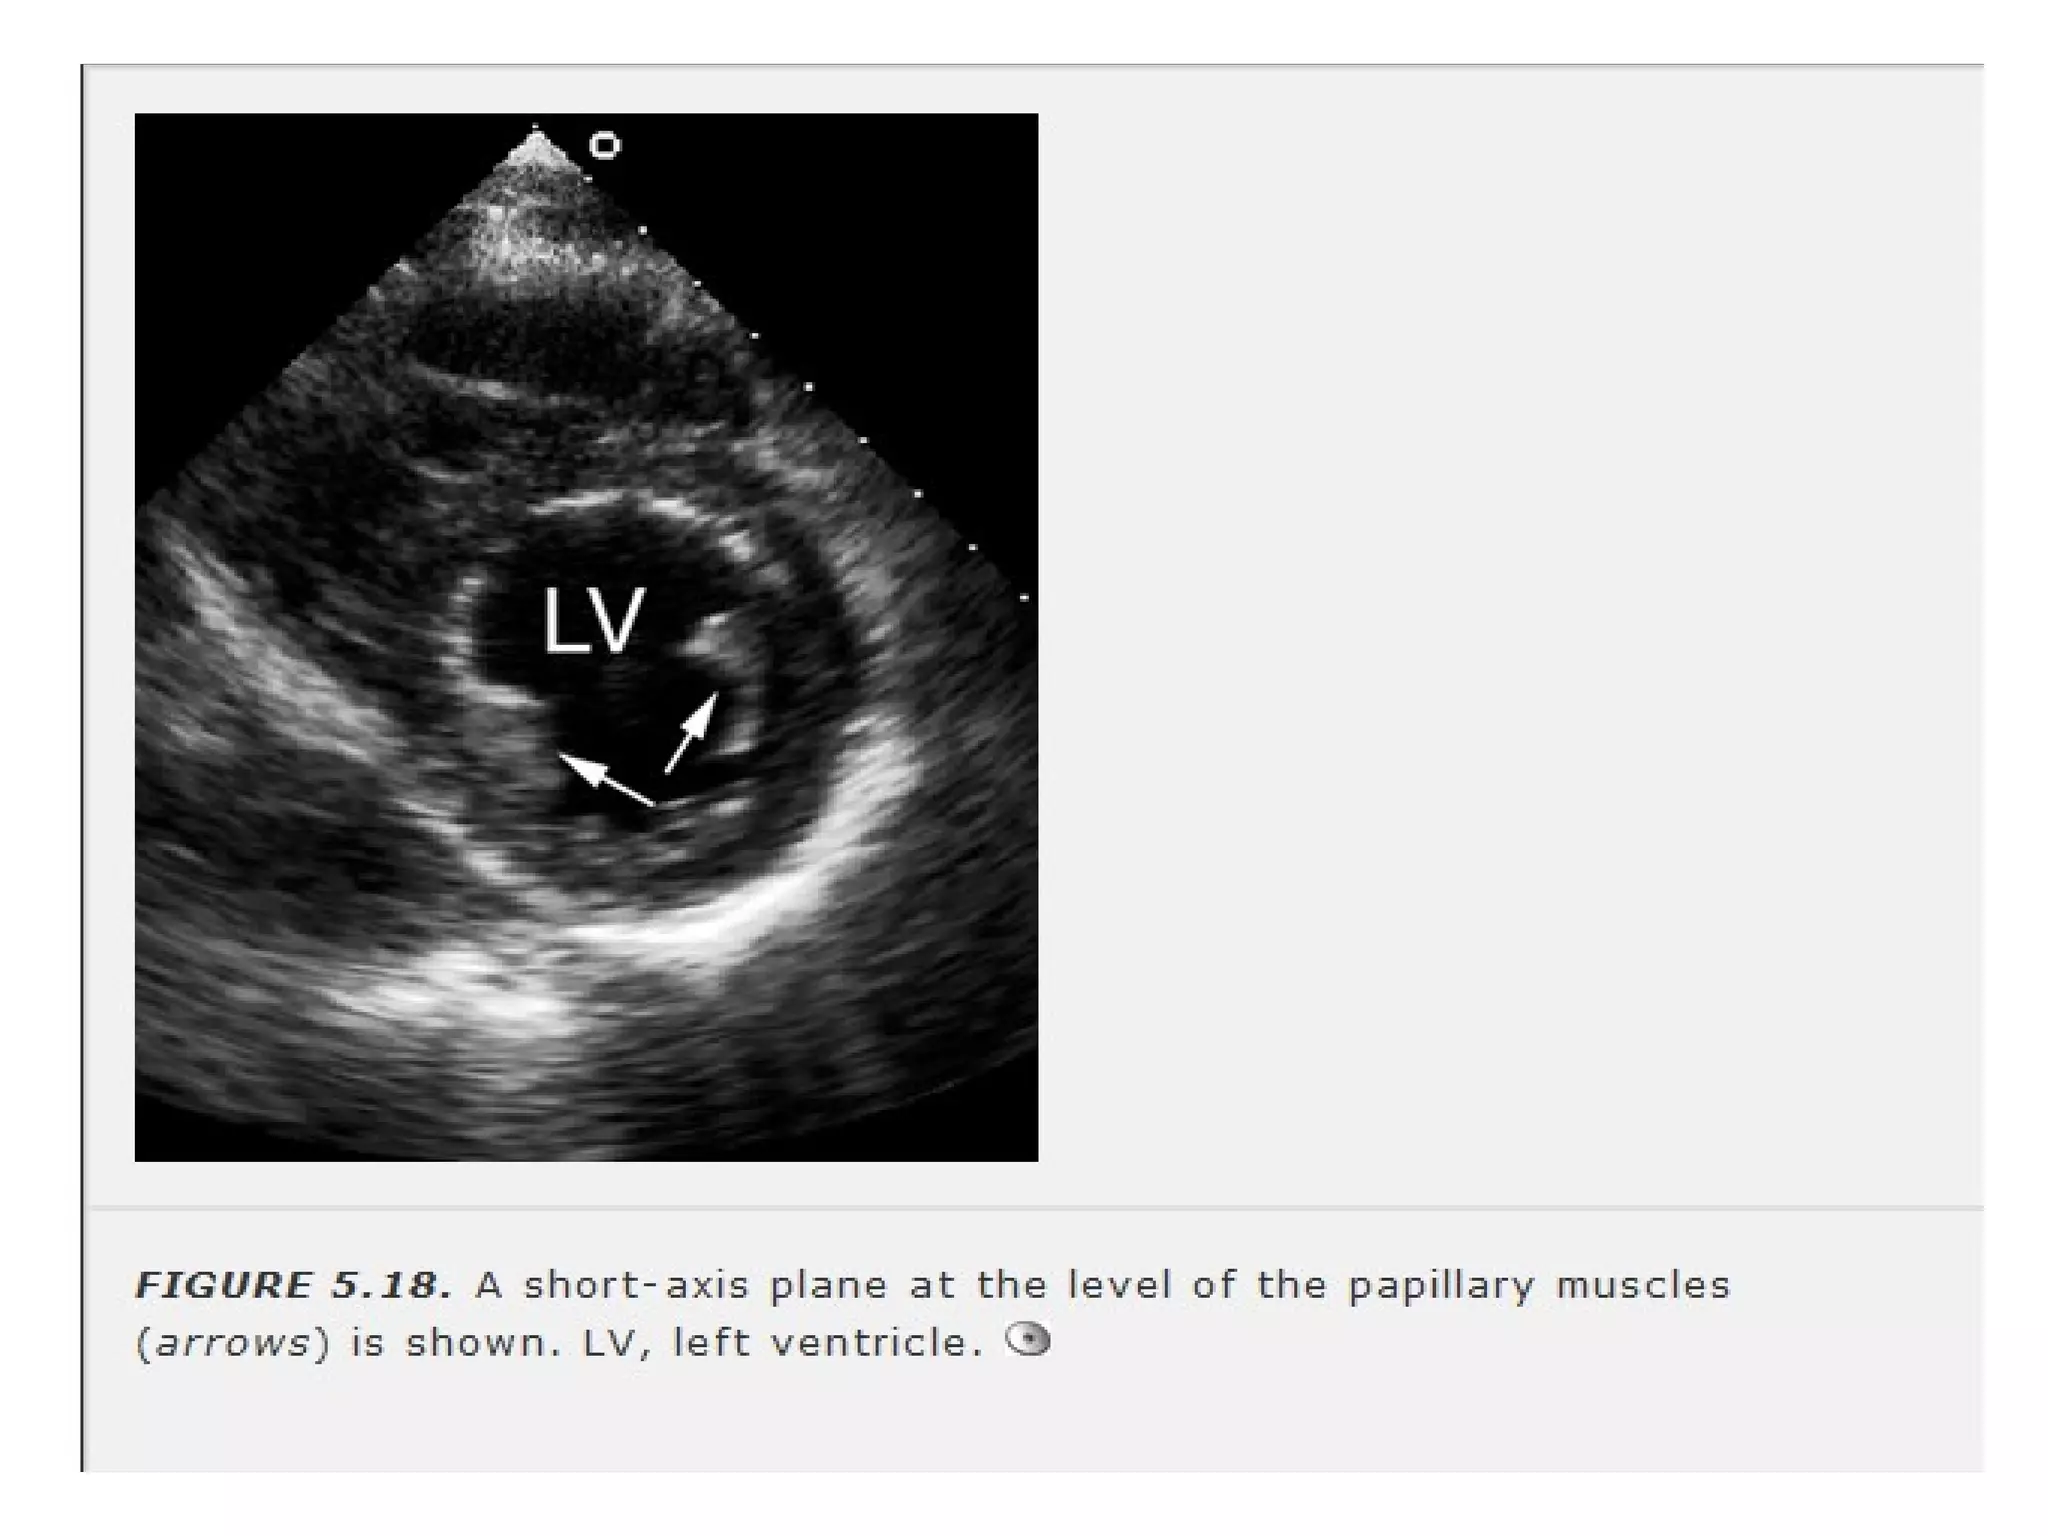

• Papillary muscle level -

• clockwise rotationof 90 degrees • Pts lateral wall I placed to the observer”s right • LV is displayed as if viewed from apex • Apical level • Papillary muscle level - • Mitral valve level- Precise recording of mitral orifice in pts with MS.